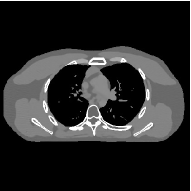

This section compares the reconstruction quality and runtime among the proposed MBIR method, PWLS-ST-, and other three MBIR methods, PWLS-EP, PWLS-DL, and PWLS-ST-. Table I shows that, for both 2D and 3D sparse-view CT reconstructions of the XCAT phantom, the proposed PWLS-ST- model outperforms PWLS-EP and PWLS-ST- in terms of RMSE. In addition, PWLS-ST- using a square transform (of size ) achieves lower RMSE than PWLS-DL using an overcomplete dictionary (of size ) for 2D sparse-view reconstructions. Fig. 3(a) and Fig. 4 show the reconstructed images for 2D and 3D phantom experiments, with different reconstruction models and different number of views. (See the corresponding error maps in the supplement.) The proposed PWLS-ST- consistently gives more accurate image reconstructions compared to other MBIR methods. Specifically, PWLS-ST- has smaller errors in the heart region (see zoom-ins in Fig. 3(a)) of 2D reconstructions than PWLS-DL and PWLS-ST-. In addition, compared to PWLS-ST-, PWLS-DL and PWLS-ST- have some ringing artifacts around the edges with high transition, e.g., edges between air and soft tissues. (See a comparison of profiles of PWLS-ST- and PWLS-ST- in the supplement.) In particular, PWLS-ST- and PWLS-DL give more visible ringing artifacts for 2D reconstruction from fewer views, and PWLS-ST- has these ringing artifacts for 3D reconstructions regardless of the number of views (see zoom-ins in Fig. 4). Table II reports runtimes of different MBIR methods in reconstructing the -views XCAT phantom scan. (FBPConvNet is a non-MBIR method and its runtime for processing a image is approximately one second with a TITAN Xp GPU.) While providing better reconstruction quality, the proposed Algorithm 1 of PWLS-ST- has shorter runtime compared to the algorithms of PWLS-DL and PWLS-ST- in Section III-A. Similar to the PWLS-EP algorithm, the reconstruction time of the PWLS-DL, PWLS-ST-, and PWLS-ST- algorithms can be further reduced by using ordered subsets [51].

Fig. 3(b) shows that when tested on the clinical scan data, the proposed PWLS-ST- method improves reconstruction quality in terms of noise and artifacts removal (e.g., see zoom-ins for soft-issue regions), and edge preservation (e.g., see zoom-ins for bone regions), compared to PWLS-EP and PWLS-ST-. Compared to PWLS-DL, PWLS-ST- achieves comparable image quality, but requires less computational complexity.

The benefit of the proposed PWLS-ST- over PWLS-ST- can be explained when there exist some outliers for some : in (12) gives equal emphasis to all sparse codes – from small to large coefficients that generally correspond to edges in low- and high-contrast regions, respectively – in estimating ; however, PWLS-ST- adjusts to mainly minimize the outliers, i.e., it may not pay enough attention to reconstruct regions with small coefficients. The histogram results in Fig. 1 reveal model mismatch of PWLS-ST- over the iterations. Fig. 3, Fig. 4, and Table I show that PWLS-ST- can moderate model mismatch, and provides more accurate reconstruction than PWLS-ST-.

| (a) 2D fan-beam CT experiments |